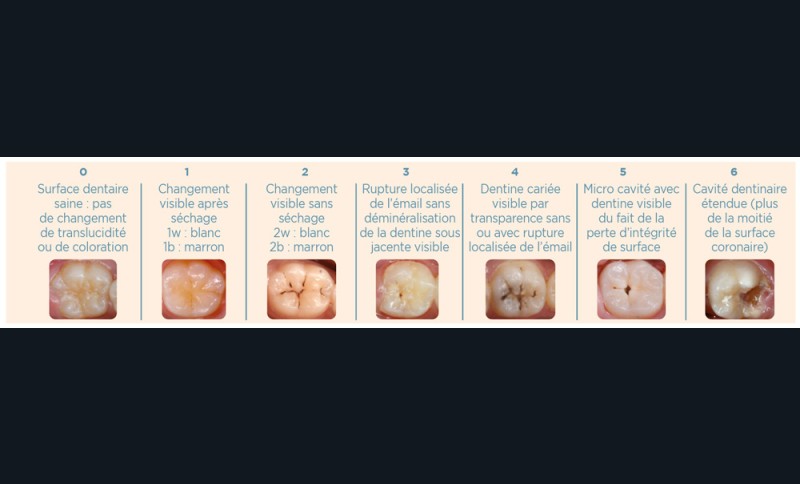

FAUX. Le diagnostic précoce des lésions carieuses se base sur un diagnostic clinique visuel précis à l’aide des classifications visuelles internationales (ICDAS ou ICCMS) et de l’utilisation d’aides optiques (loupes, microscope, caméra avec signal fluorescent ou non) et sur un diagnostic radiographique (à l’aide de deux bitewing, l’un à droite l’autre à gauche) (fig. 1).

• Traitement non invasif : après avoir réalisé un contrôle de plaque dentaire (révélateur de plaque, apprentissage et motivation à l’hygiène bucco-dentaire), ce traitement est mis en place lorsque la lésion carieuse est active mais non cavitaire (ICDAS 1 et 2). Dans ce cas, le chirurgien-dentiste utilise des thérapeutiques qui permettront de modifier le biofilm buccal du patient (par exemple, les probiotiques, l’arginine), et/ou des produits de reminéralisation (par exemple, Casein Phosphopeptide-Amorphous Calcium Phosphate) et/ou du Silver Diamine Fluoride (SDF).

• Traitement micro invasif : il s’agit essentiellement de l’érosion/infiltration (fig. 5), mais une alternative peut également être utilisée pour les mêmes indications : le traitement de micro abrasion (fig. 6). L’indication première de cette technique est d’arrêter la progression des lésions carieuses non cavitaires lors d’une déminéralisation de l’émail (ICDAS 2) ou cavitaires au niveau de l’émail sans déminéralisation de la dentine sous-jacente (ICDAS 3) d’un patient à faible risque carieux.

• Traitement invasif a minima : il concerne les lésions carieuses cavitaires ou non avec atteinte dentinaire (à partir du 1/3 moyen dentinaire), soit ICDAS 3 à 6. Dans ce cas, la priorité est de préserver la dent d’une effraction pulpaire éventuelle (recommandations de l’ESE) [4]. C’est pourquoi, lors du traitement de lésions carieuses profondes (ICDAS 4 à 6), il faut dans tous les cas réaliser une éviction sélective, réaliser une préparation a minima (favoriser les préparations de type fente (« slot ») ou tunnel lorsque l’indication se pose) et utiliser un matériau de restauration de choix, soit composite, soit un ciment verre ionomère (CVI), soit des matériaux à base de silicate de calcium ou encore les nouveaux composites enrichis en minéraux (fig. 7 à 9). Ces préparations a minima peuvent être réalisées avec des fraises de petits diamètres (fig. 10 et 11).